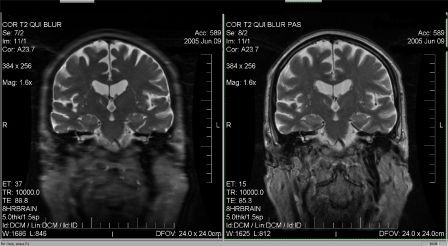

Tu as raison de préciser Higgins que ce n'est pas l'artéfact de troncature... Cet artéfact est dû à une trop grande différence de pondération entre le TE effectif (TE eff) qui va coder pour les lignes centrales de l'espace de Fourier et la pondération du dernier écho du train d'échos (TE max) qui lui, va coder les lignes périphériques de l'espace K. Dans l'exemple ci-dessous, vous pouvez trouver une image volontairement mal paramétrée pour créer du blurring (Train d'écho trop grand) et une image optimisée (paramètres réglés pour que le TE effectif soit au centre du train d'échos). Cet artéfact est souvent confondu avec l'artéfact de mouvement ou est souvent pris pour une mauvaise résolution spatiale...

Pièces jointes : |

blurring anonyme.jpg [ 25.21 Kio | Consulté 49948 fois ]